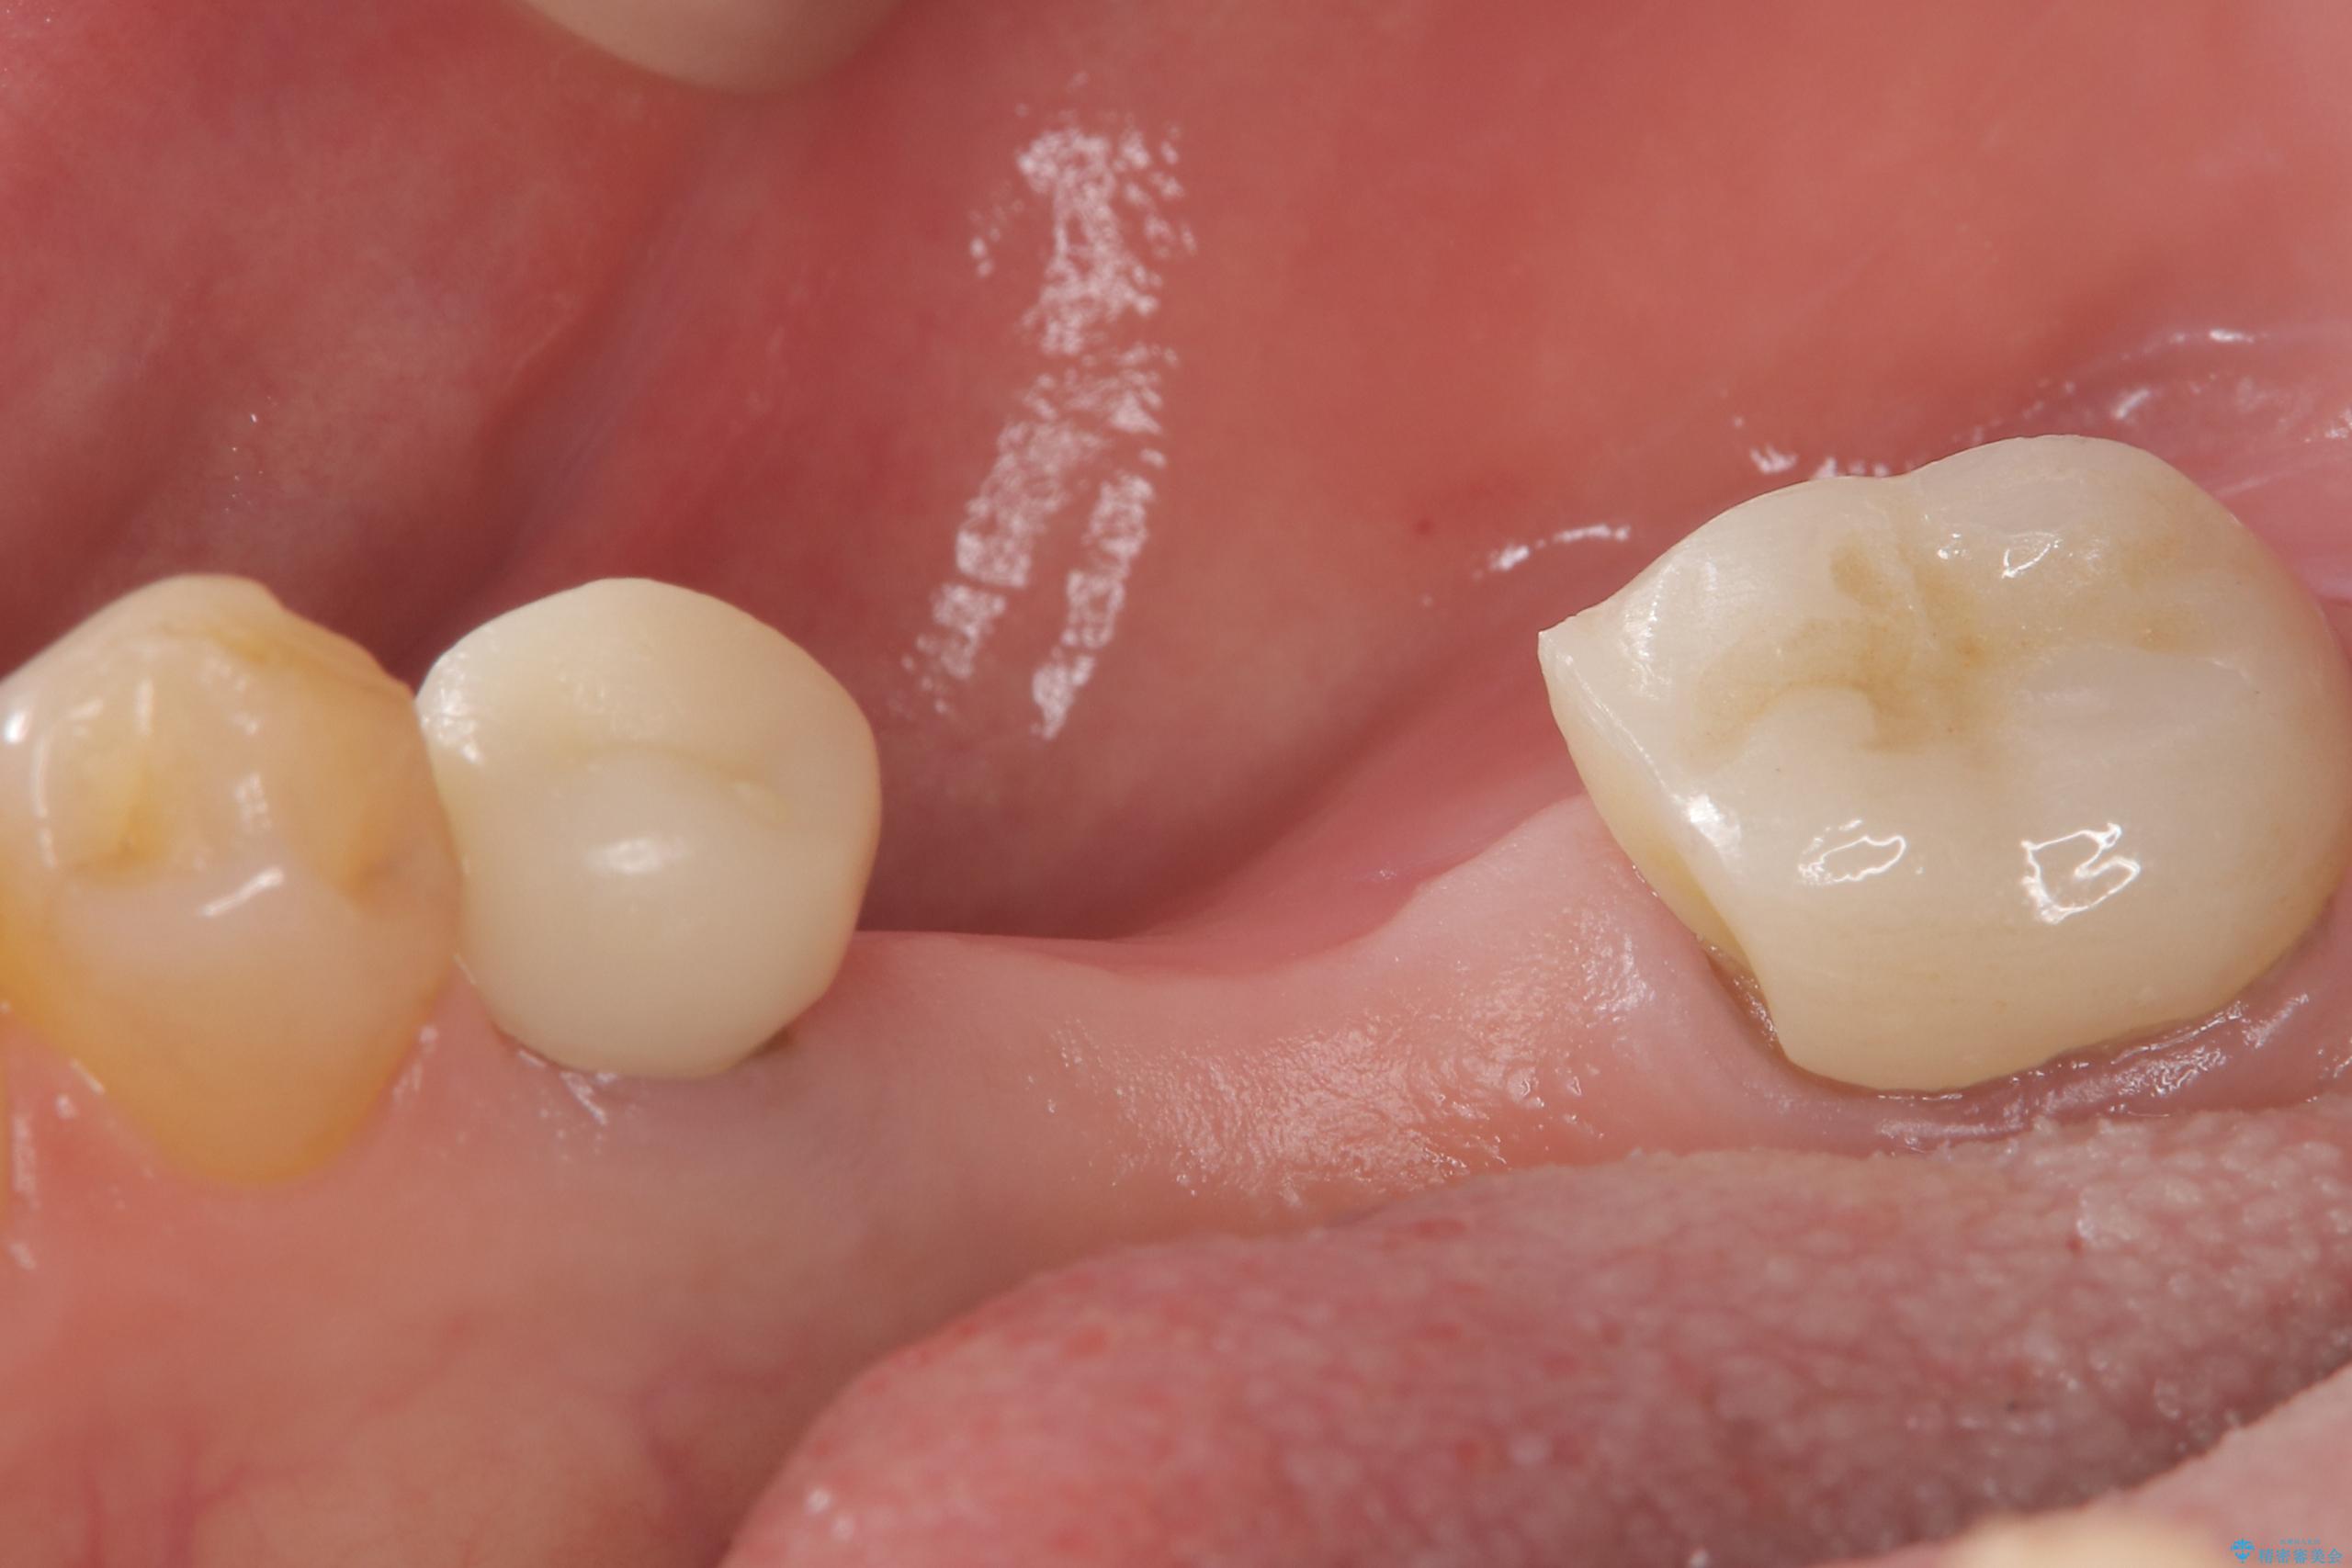

- 主訴:つい先日入れたセラミック(ジルコニア)ブリッジが奥歯部分で割れた。いつも同じ場所で壊れる。これで3度目。

セラミックに比べ、割れづらい金属(ゴールドでのブリッジのやり替えとなりました。

セラミックに比べ、破折リスクの少ない金属を使用したブリッジでのやり替えとなりました。

右下5番は支台歯CR築造を行っています。